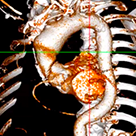

江西省人民医院李林锋教授代表洪浪教授团队,分享了一例EF值极低的TAVI手术。患者为69岁男性,术前超声心动图提示主动脉瓣重度狭窄合并微量反流,二叶瓣(Type 1型)合并重度钙化,主动脉瓣前向血流Vmax 4.1m/s,PG 65mmHg,主动脉瓣口面积0.3cm2,EF 19%,术前CT分析提示LCA 11mm,RCA 9.2mm,右冠风险稍高,横位心。

最终,手术团队决定采用静脉镇静的“极简式”麻醉方案,在经胸超声联合DAS指导瓣膜植入。首先采用了12mm外周球囊预扩主动脉瓣口,经胸超声评估,扩张后EF由19%上升至25%,血氧饱和度由93%上升至99%;但初次扩张后患者即刻出现阿斯综合征,经心肺复苏后生命体征回复平稳;随后再次使用18mm球囊预扩,EF进一步上升至30%。在此心功能条件下,决定实施TAVI手术。由于患者入路仅5.4mm,选择植入VitaFlow®一代24mm瓣膜。